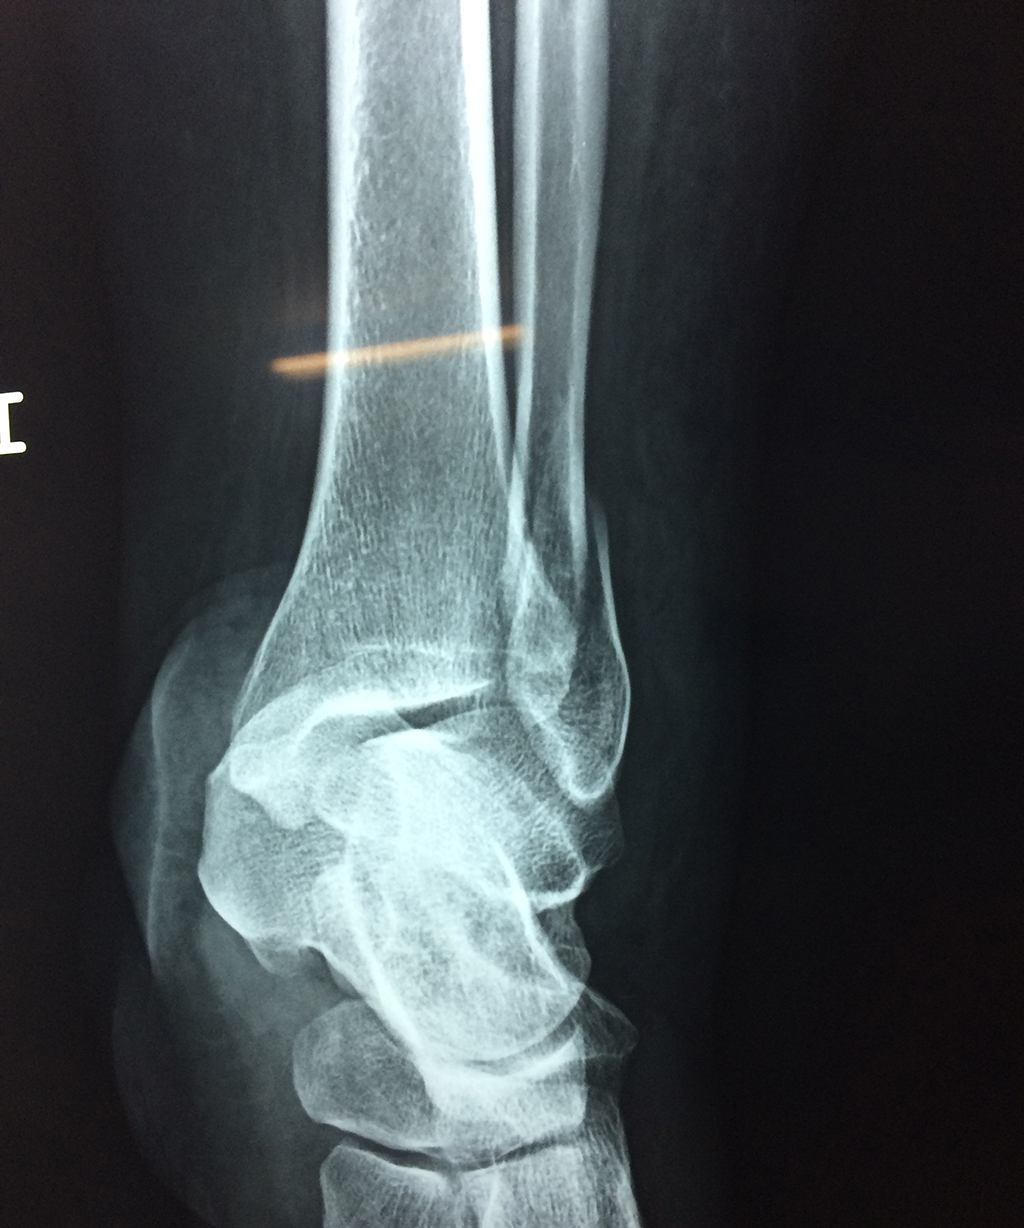

Una fractura de tobillo es la rotura de uno o más de los huesos del tobillo. Estas fracturas pueden ser:

Algunas fracturas de tobillo pueden requerir cirugía si:

- Los extremos de los huesos están desalineados entre sí (desplazados).

- La fractura se extiende hasta la articulación del tobillo (fractura intra-articular).

- Los tendones o ligamentos (tejidos que sujetan los músculos y los huesos entre sí) están rotos.

- El médico cree que sus huesos probablemente no sanen apropiadamente sin cirugía.

- El médico considera que la cirugía puede permitirle una recuperación más rápida y confiable.